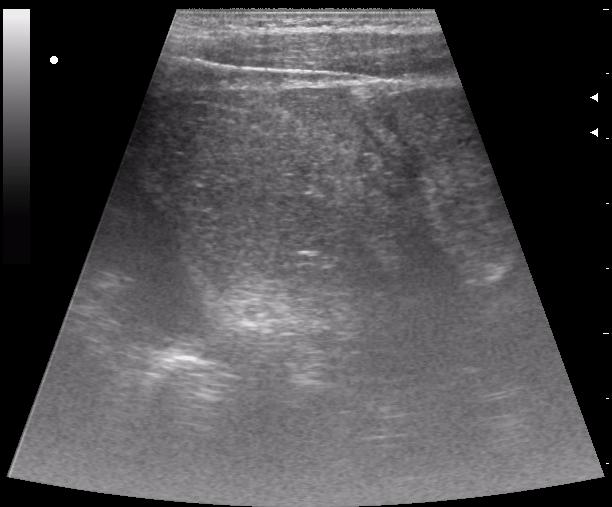

сегодня был селезёночный день.